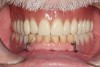

The final denture (Figure 17 and Figure 18) was returned to the restorative dentist about 2 weeks after the try-in appointment. When patient returned for delivery of the denture (Figure 19 through Figure 21), he expressed complete satisfaction with both the fit and appearance. No adjustment was required to compensate for sore spots. In general, the author has found that delivery of the digital dentures is faster than when using a conventional fabrication process.

Figure 19 The final denture fit perfectly when it was tried in.

Figure 19

Figure 20 The patient was delighted with both the fit and the appearance of the final denture.

Figure 20

Figure 21 Facial view of the final denture.

Figure 21